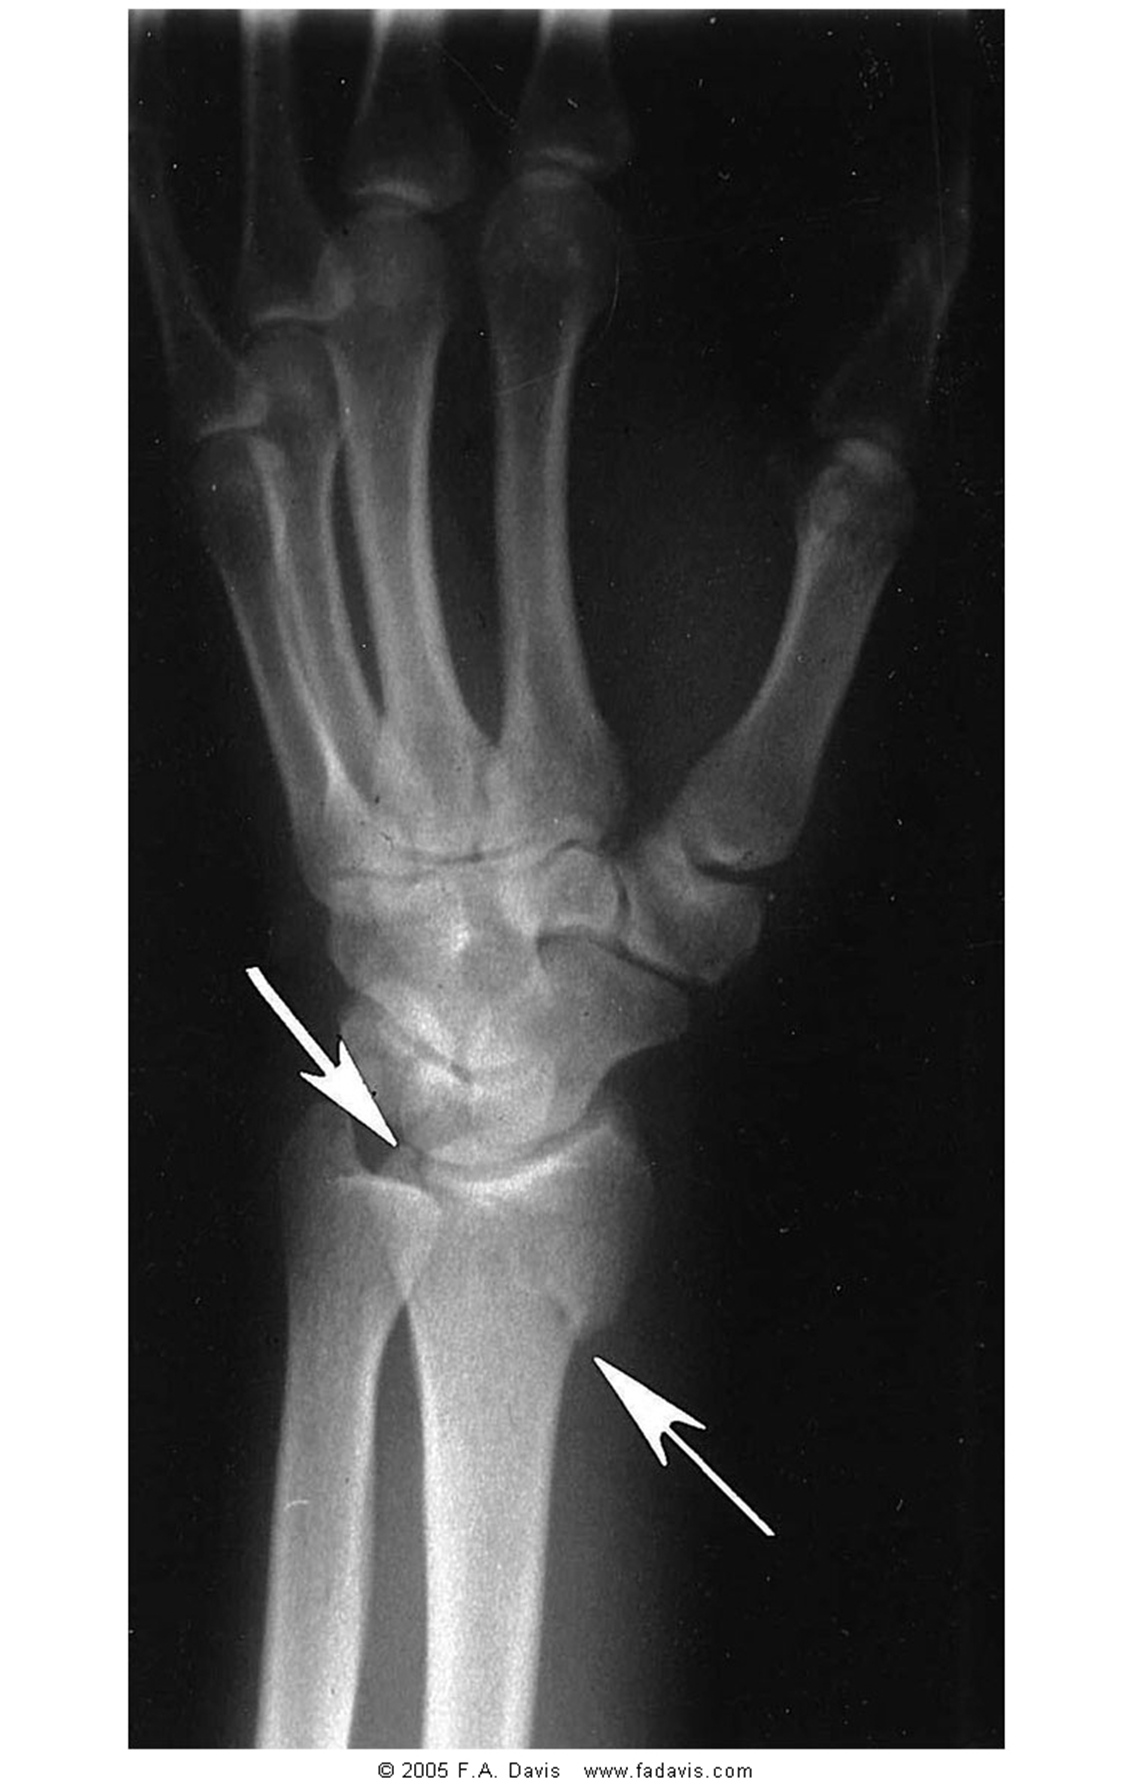

describe this fx using anatomic site and extent

intra-articular